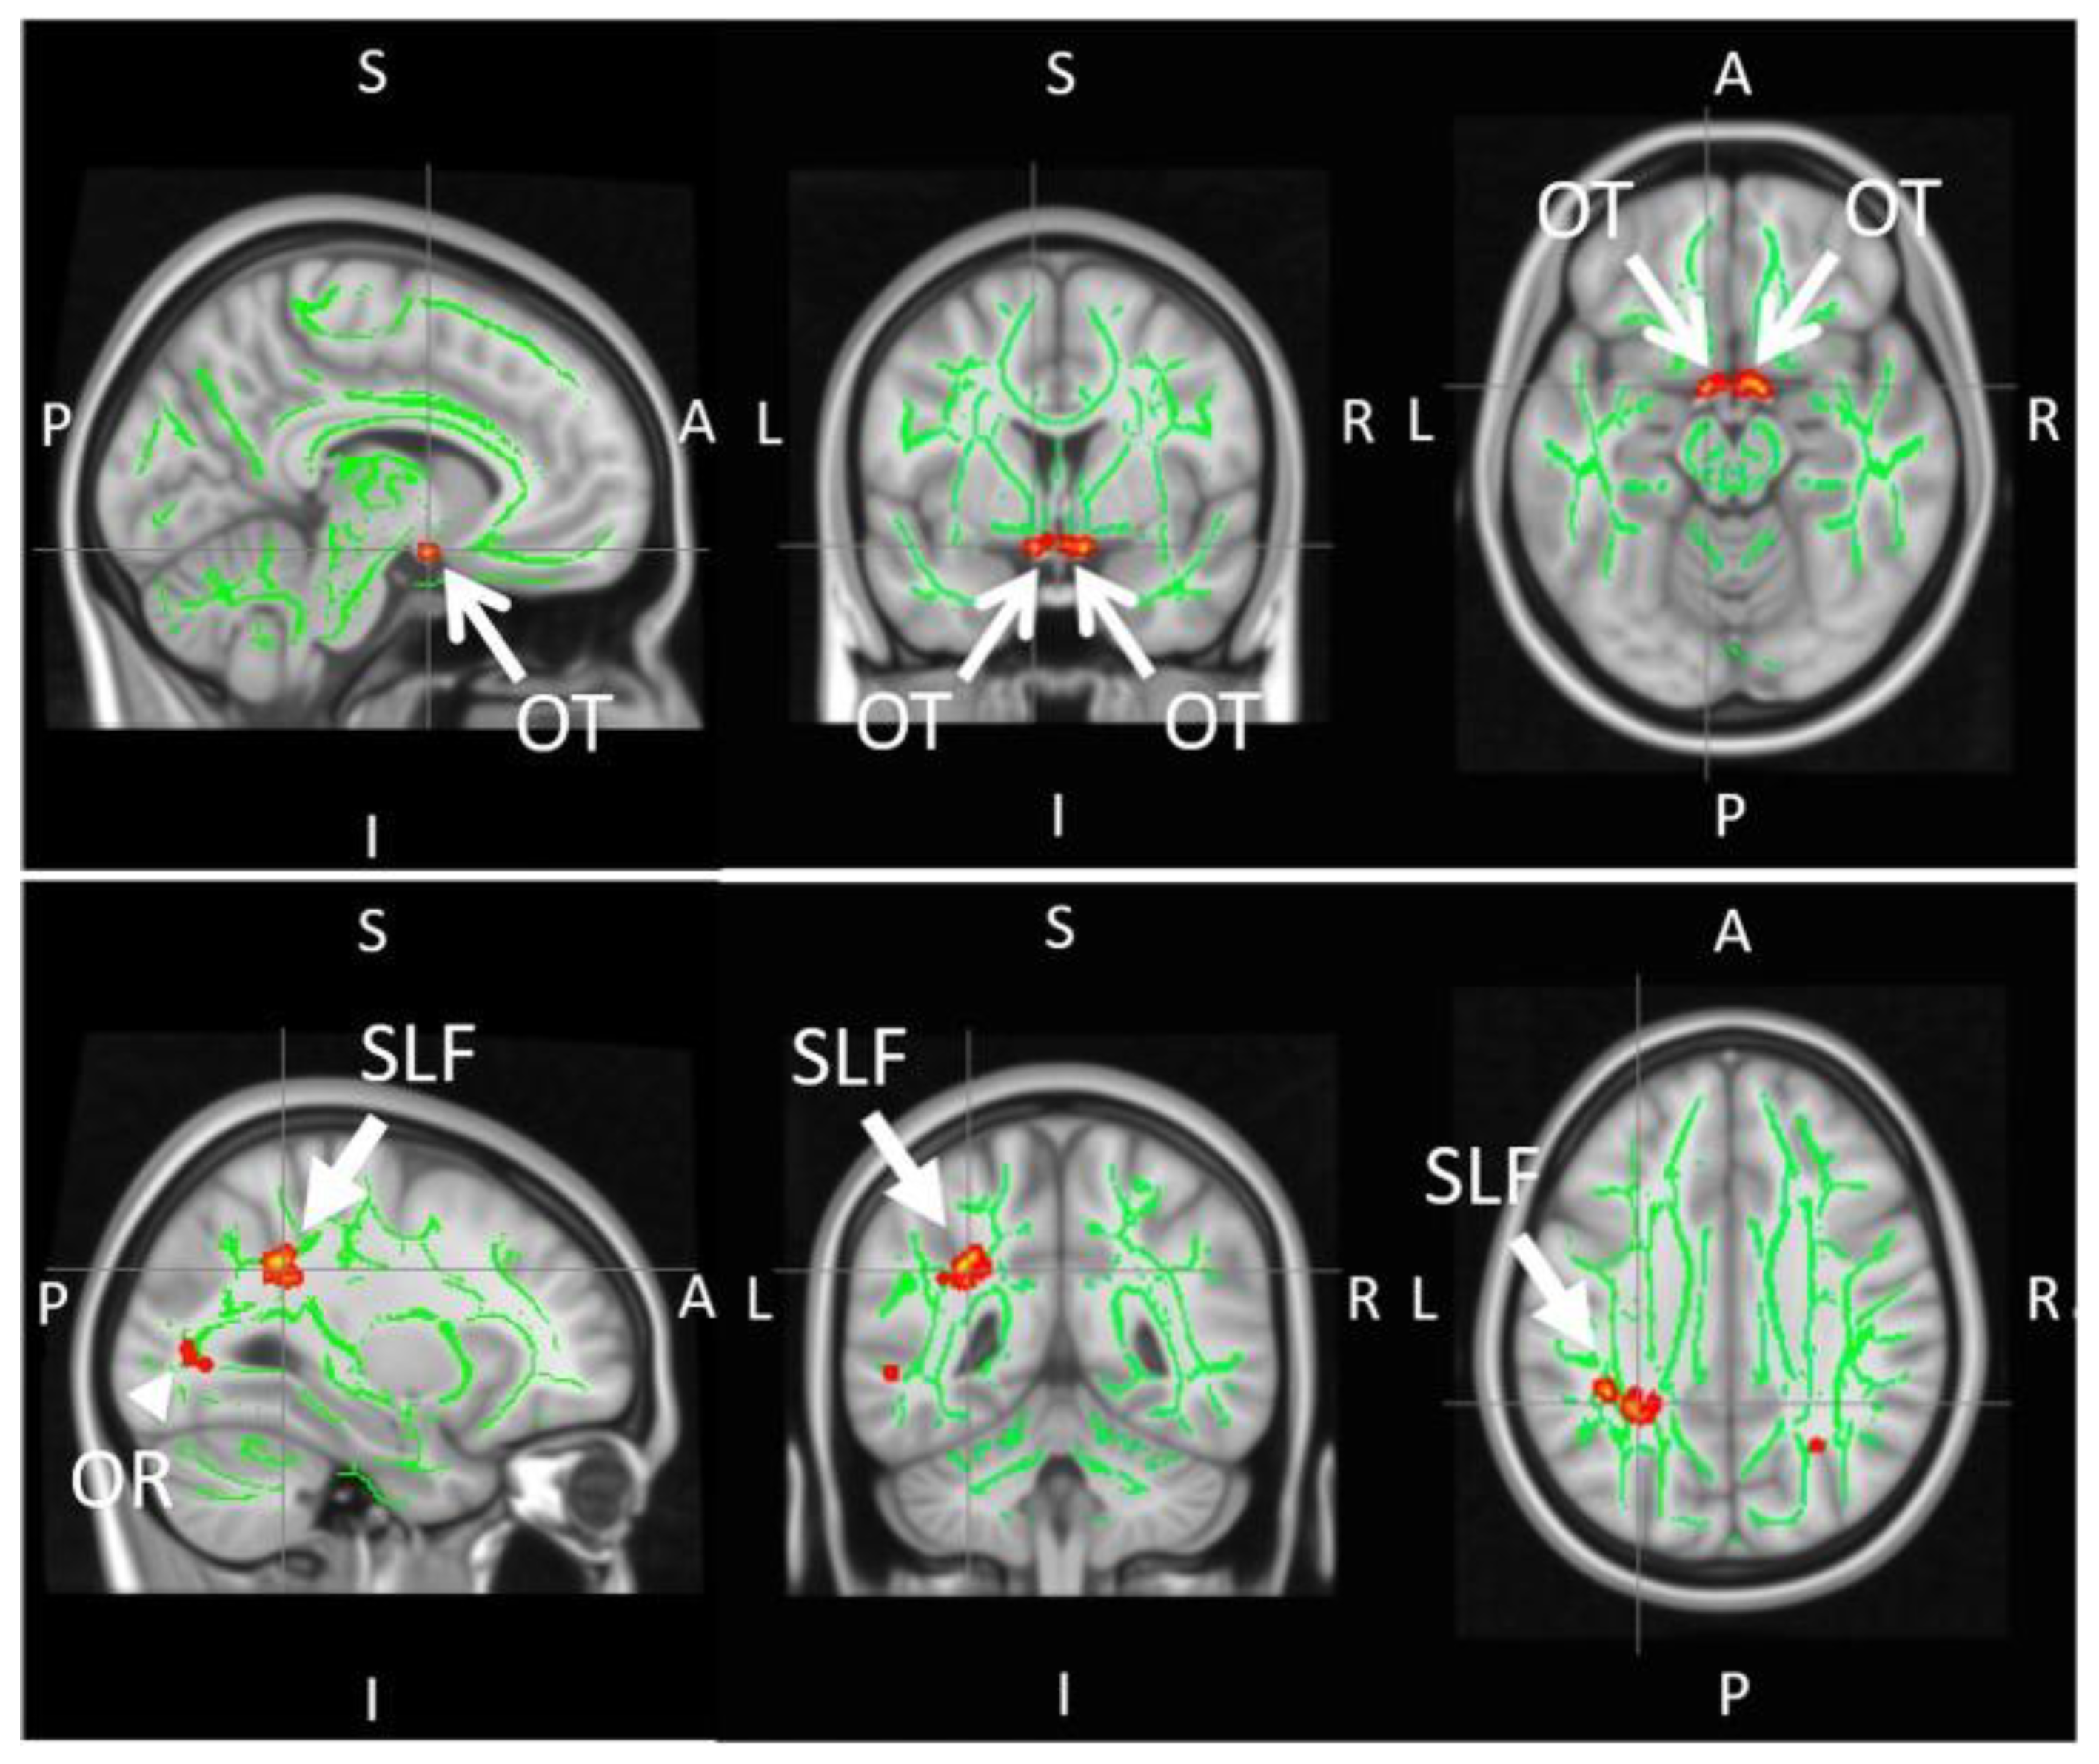

- Giorgio, A.; Zhang, J.; Costantino, F.; De Stefano, N.; Frezzotti, P. Diffuse brain damage in normal tension glaucoma. Hum. Brain Mapp. 2018, 39, 532–541. [Google Scholar] [CrossRef]

- Frezzotti, P.; Giorgio, A.; Motolese, I.; De Leucio, A.; Iester, M.; Motolese, E.; Federico, A.; De Stefano, N. Structural and Functional Brain Changes beyond Visual System in Patients with Advanced Glaucoma. PLoS ONE 2014, 9, e105931. [Google Scholar] [CrossRef]

- Qu, X.; Wang, Q.; Chen, W.; Li, T.; Guo, J.; Wang, H.; Zhang, X.; Wang, Y.; Wang, N.; Xian, J. Combined machine learning and diffusion tensor imaging reveals altered anatomic fiber connectivity of the brain in primary open-angle glaucoma. Brain Res. 2019, 1718, 83–90. [Google Scholar] [CrossRef]

- Wang, R.; Tang, Z.; Sun, X.; Wu, L.; Wang, J.; Zhong, Y.; Xiao, Z. White matter abnormalities and correlation with severity in normal tension glaucoma: A whole brain atlas-based diffusion tensor study. Investig. Opthalmol. Vis. Sci. 2018, 59, 1313–1322. [Google Scholar] [CrossRef]

- Miller, N.; Liu, Y.; Krivochenitser, R.; Rokers, B. Linking neural and clinical measures of glaucoma with diffusion magnetic resonance imaging (dMRI). PLoS ONE 2019, 14, e0217011. [Google Scholar] [CrossRef]